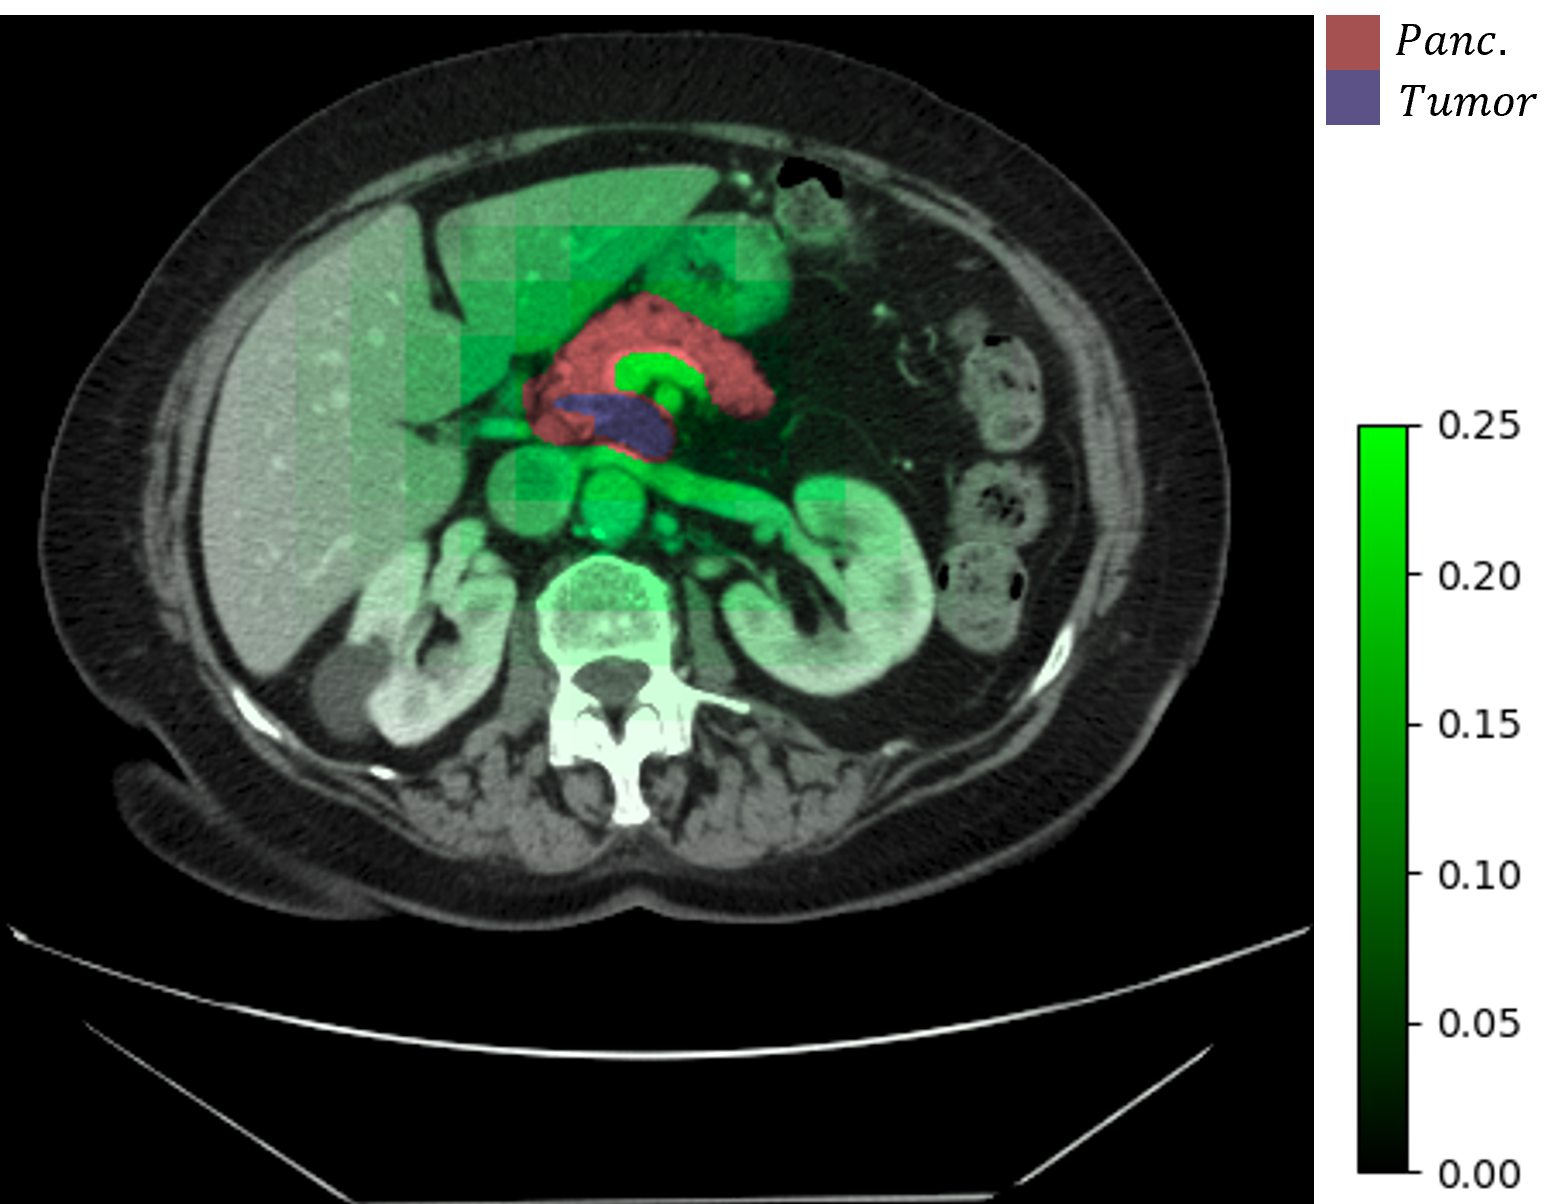

Refer to caption

(a) Δωθa(I)Δsubscriptsuperscript𝜔𝑎subscript𝜃𝐼\Delta\omega^{a}_{\mathcal{H}_{\theta}}(I) and labels

(b) ΔωθI(ai,aj)Δsubscriptsuperscript𝜔𝐼subscript𝜃subscript𝑎𝑖subscript𝑎𝑗\Delta\omega^{I}_{\mathcal{H}_{\theta}}(a_{i},a_{j})

Figure 6: Visualization of changing ωθa,Isubscriptsuperscript𝜔𝑎𝐼subscript𝜃\omega^{a,I}_{\mathcal{H}_{\theta}} depends on different image or architecture inputs. We use our 5GB and 7GB architectures as aisubscript𝑎𝑖a_{i} and ajsubscript𝑎𝑗a_{j} in 6(b). Results are aggregated based on sliding-window averaging with a stride size of sixteen.

HyperNet Analysis. We provide some insights into the behavior of the HyperNet \mathcal{H} and its output ωθa,Isubscriptsuperscript𝜔𝑎𝐼subscript𝜃\omega^{a,I}_{\mathcal{H}_{\theta}}. While it is difficult to interpret the channel-wise weights individually, we can observe how ωθa,Isubscriptsuperscript𝜔𝑎𝐼subscript𝜃\omega^{a,I}_{\mathcal{H}_{\theta}} changes with different inputs. To do so, we fix the architecture vector larchsubscript𝑙archl_{\textrm{arch}} and provide \mathcal{H} with limagesubscript𝑙imagel_{\textrm{image}} generated from different patches. Similarly, we can fix limagesubscript𝑙imagel_{\textrm{image}} and change larchsubscript𝑙archl_{\textrm{arch}} to observe the differences based on architectures. We observe that the majority of the patches yields very similar ωθa,Isubscriptsuperscript𝜔𝑎𝐼subscript𝜃\omega^{a,I}_{\mathcal{H}_{\theta}}, while a few patches have very different weights. To quantify, we define two metric:

where Δωθa(I)Δsubscriptsuperscript𝜔𝑎subscript𝜃𝐼\Delta\omega^{a}_{\mathcal{H}_{\theta}}(I) measures the 2subscript2\mathcal{L}_{2} distance between ωa,Isubscriptsuperscript𝜔𝑎𝐼\omega^{a,I}_{\mathcal{H}}, which is from a specific patch I𝐼I, and ω¯asubscriptsuperscript¯𝜔𝑎\overline{\omega}^{a}_{\mathcal{H}}, which is the average weights over all patches in a given volume; ΔωθI(ai,aj)Δsubscriptsuperscript𝜔𝐼subscript𝜃subscript𝑎𝑖subscript𝑎𝑗\Delta\omega^{I}_{\mathcal{H}_{\theta}}(a_{i},a_{j}) measures the difference between weights generated from architecture aisubscript𝑎𝑖a_{i} and ajsubscript𝑎𝑗a_{j} on the same patch.

We visualize these two metrics on a sample CT volume in Fig. 6, along with the segmentation labels. For patches that are not relevant to the labels, \mathcal{H} generates very similar ωθa,Isubscriptsuperscript𝜔𝑎𝐼subscript𝜃\omega^{a,I}_{\mathcal{H}_{\theta}}; on the other hand, patches that contain labels yield significantly different weights. Furthermore, ΔωθI(ai,aj)Δsubscriptsuperscript𝜔𝐼subscript𝜃subscript𝑎𝑖subscript𝑎𝑗\Delta\omega^{I}_{\mathcal{H}_{\theta}}(a_{i},a_{j}) is also significant on foreground patches, and minimum on background patches. This suggests that \mathcal{M} and \mathcal{H} implicitly partitions potential foreground regions, which is a strategy similar to foreground oversampling used in methods like nnU-Net [19]. While our method does not employ explicit foreground oversampling, the HyperNet design appears to automate such a strategy. For more details on the visualization of ωθa,Isubscriptsuperscript𝜔𝑎𝐼subscript𝜃\omega^{a,I}_{\mathcal{H}_{\theta}}, please refer to the Supplemental Material.